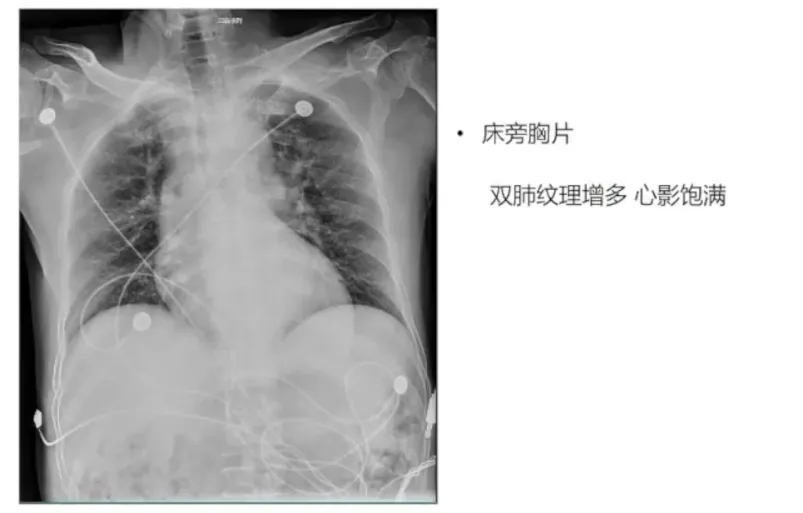

射血分数保留型心衰

患者66岁老年男性,急性病程胸痛5个小时入院就诊。考虑到患者年龄、性别,及其高血压、高脂血症、吸烟、饮酒等心血管危险因素,首先怀疑急性冠脉综合征可能,行冠脉造影排除大血管狭窄后,行腺苷负荷超声心动图检查。患者CFR值1.88,确诊为冠状动脉微循环障碍(CMVD),初步考虑患者胸痛症状与CMVD相关。

➤心脏超声分析:超声心动图是筛查心脏淀粉样变性(CA)的重要工具,当出现左心室厚度>12mm以及Ⅱ级以上舒张功能障碍、左心室整体纵向应变降低伴心尖保留现象等“红旗征”时,需要高度怀疑CA可能。本例患者超声心动图提示仅室间隔基底段增厚,存在舒张功能障碍但并未达到充盈受限,无特异性CA表现,应变超声心动图“心尖保留”模式不明显。结合其临床表现及相关检查结果,考虑可能为CA早期阶段。